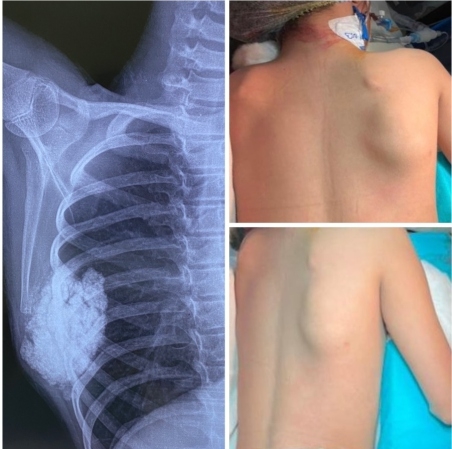

Calcinosis mimicking tumor: A rare case report

Suyog Wagh , Sudhir Sharan , Arvind Goregaonkar , Aditya Mugutrao , Kishan Panjwani ………………………………p.69-73